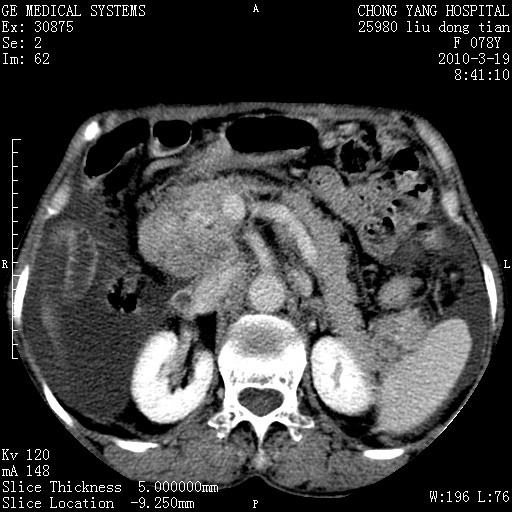

标题: CT25199:F 78Y 腹胀半年 消瘦乏力 [打印本页]

胆囊壁增厚并明显强化,胆囊癌伴多发转移瘤可能性大,淋巴瘤不除外,右肾囊肿,胸腹水.

考虑nhl,肝、脾、腹膜腔及腹膜后多发淋巴结受侵,腹水,右肾囊肿,慢性胆囊炎,右侧少量胸腔积液。

首先考虑恶性淋巴瘤 。

胰头有肿块形成,胰头ca伴肝脾、腹膜腹膜后转移

胆囊有软组织影有强化,支持胆囊癌,肝脾、腹膜后淋巴结转移。

nhl的淋巴结多围绕主动脉,而且主动脉会移位,所以不考虑nhl。

分开来讲:肝左叶、尾叶病灶有不均强化像肝癌;

脾脏病灶无强化,像多发囊肿或淋巴管瘤,不除外淋巴瘤(低强化);

胆囊增生性病变:胆囊癌,腺肌增生症,慢性胆囊炎;

肝门、胰腺头、腹膜后多个团块: 淋巴瘤,转移;

腔静脉肝内段细小有无布加可能?

一元论最好了 淋巴瘤所致改变; 胆囊癌转移不像,胆囊周围肝组织清晰,肝癌淋巴结转移?三元论都不止。

胰头ca伴肝脾、腹膜腹膜后转移!

最后报的胰头癌多发转移,脾脏单独考虑囊肿或淋巴管瘤。